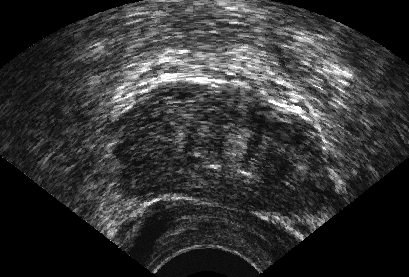

It is a challenge to validate any approach to segmentation. One has to measure the accuracy of the segment against ground-truth images. Ideally, if we have many users available to segment images, we can build “consensus segments”, or gold standard, to make more reliable measurements. Of course, this is usually not feasible with real images, for which there is no gold standard. Hence, we generated synthetic images whose gold segments were known a priori. For this reason, we used synthetic images that simulate transrectal ultrasound (TRUS).

TRUS images of prostates may be used to both diagnose and treat prostate diseases such as cancer. Starting with a set of prostate shapes , we created random segments through combinations of those priors, adding noise along with random translations and rotations, and we distorted the results with speckle noise and shadow patterns. Each image is thus created from its gold . Consequently, we can simulate user delineations by manipulating via scaling, rotation, and morphological changes, and we can simulate edits by running active contours with variable user-simulating parameters. The variability of user delineations was simulated according to several factors: error probability (), anatomical difficulty ( out of ), and the scaling factor for morphology (form to ). The user was modelled according to the level of experience (a random number from ), the user’s attention (a random number from ), and the user’s tendencies in terms of the segment size (a random number from ), whether tending to draw contours that are relatively small () or large ().

We generated 500 images from their corresponding gold-standard images111All images and their segments are available online: http://tizhoosh.uwaterloo.ca/. Furthermore, we generated 20 different segments for each image, assuming that there were 20 users. Figure 4 shows five examples of real and synthetic TRUS images. One should bear in mind that the purpose here was not to simulate the images realistically, but rather to have a base from which to generate variable segments from a perfect segment. Figure 5 shows an example of the gold segments and simulated user contours. The variability, coupled with the gold segment, is what is needed in our experiments.